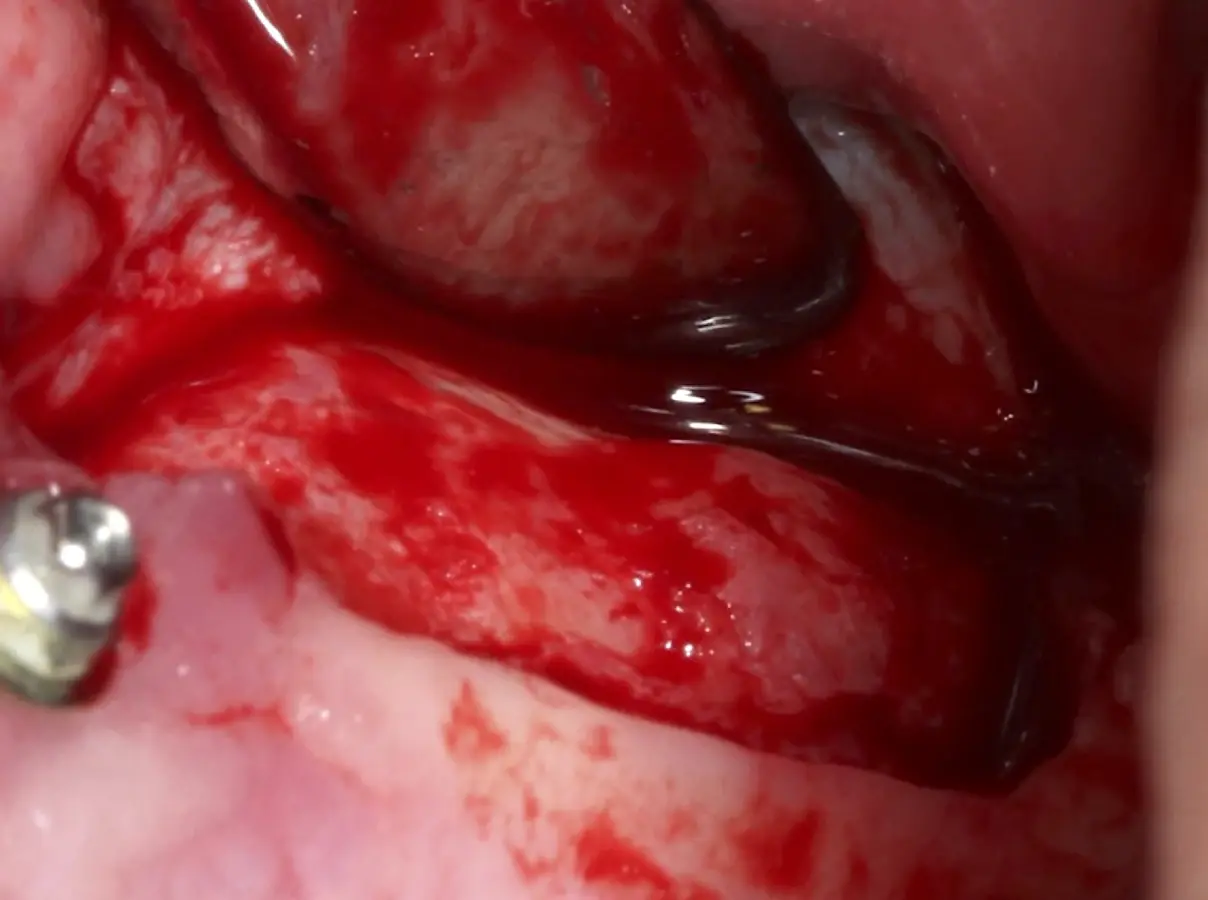

La técnica se inicia con la colocación de anestesia infiltrativa, posteriormente se realiza una incisión crestal o paracrestal con posibles liberantes verticales que deben de estar alejadas por lo menos 5 mm de los límites de la futura ventana y sobrepasar la línea mucogingival. Se realiza una elevación de colgajo, se inicia la antrostomía y antroplastía. Para ello, se emplea el inserto redondo diamantado de corte al momento de delimitar los bordes de la ventana de acceso. Luego se cambia al inserto aserrado liso de calibre fino con superficie diamantada, para profundizar y eliminar el hueso en el contorno de la ventana. Una vez que se traslucen los tejidos, se puede optar por el retiro de la tapa ósea o el levantamiento de ésta junto con la membrana.

Se inicia la elevación de la membrana de Schneider con el inserto redondeado no cortante en forma de disco, empleando movimientos suaves. El levantamiento puede complementarse con elevadores convencionales, siguiendo la dirección mesiodistal. La fase de desprendimiento inicia con el piso y sigue hacia la pared mesial para terminar, y de ser necesario, hacia la pared posterior. Existen diversos insertos con angulaciones y longitudes para mayor accesibilidad16 (Figura 1).